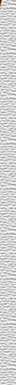

Trígono

retromolar |

Apófisis

coronoides |

Escotadura

sigmoidea |

condilar (articular) |

Ángulo

de la mandíbula |

Surco

milohiodeo |

Fosa

submandibular |

Línea

milohiodea |

sublingual |

Fosita

pterigoidea |

digástrica |

Espina

geni superior |

Porción

alveolar |

de Spix

(lingula mandibular) |

Orificio

del conducto dentario |